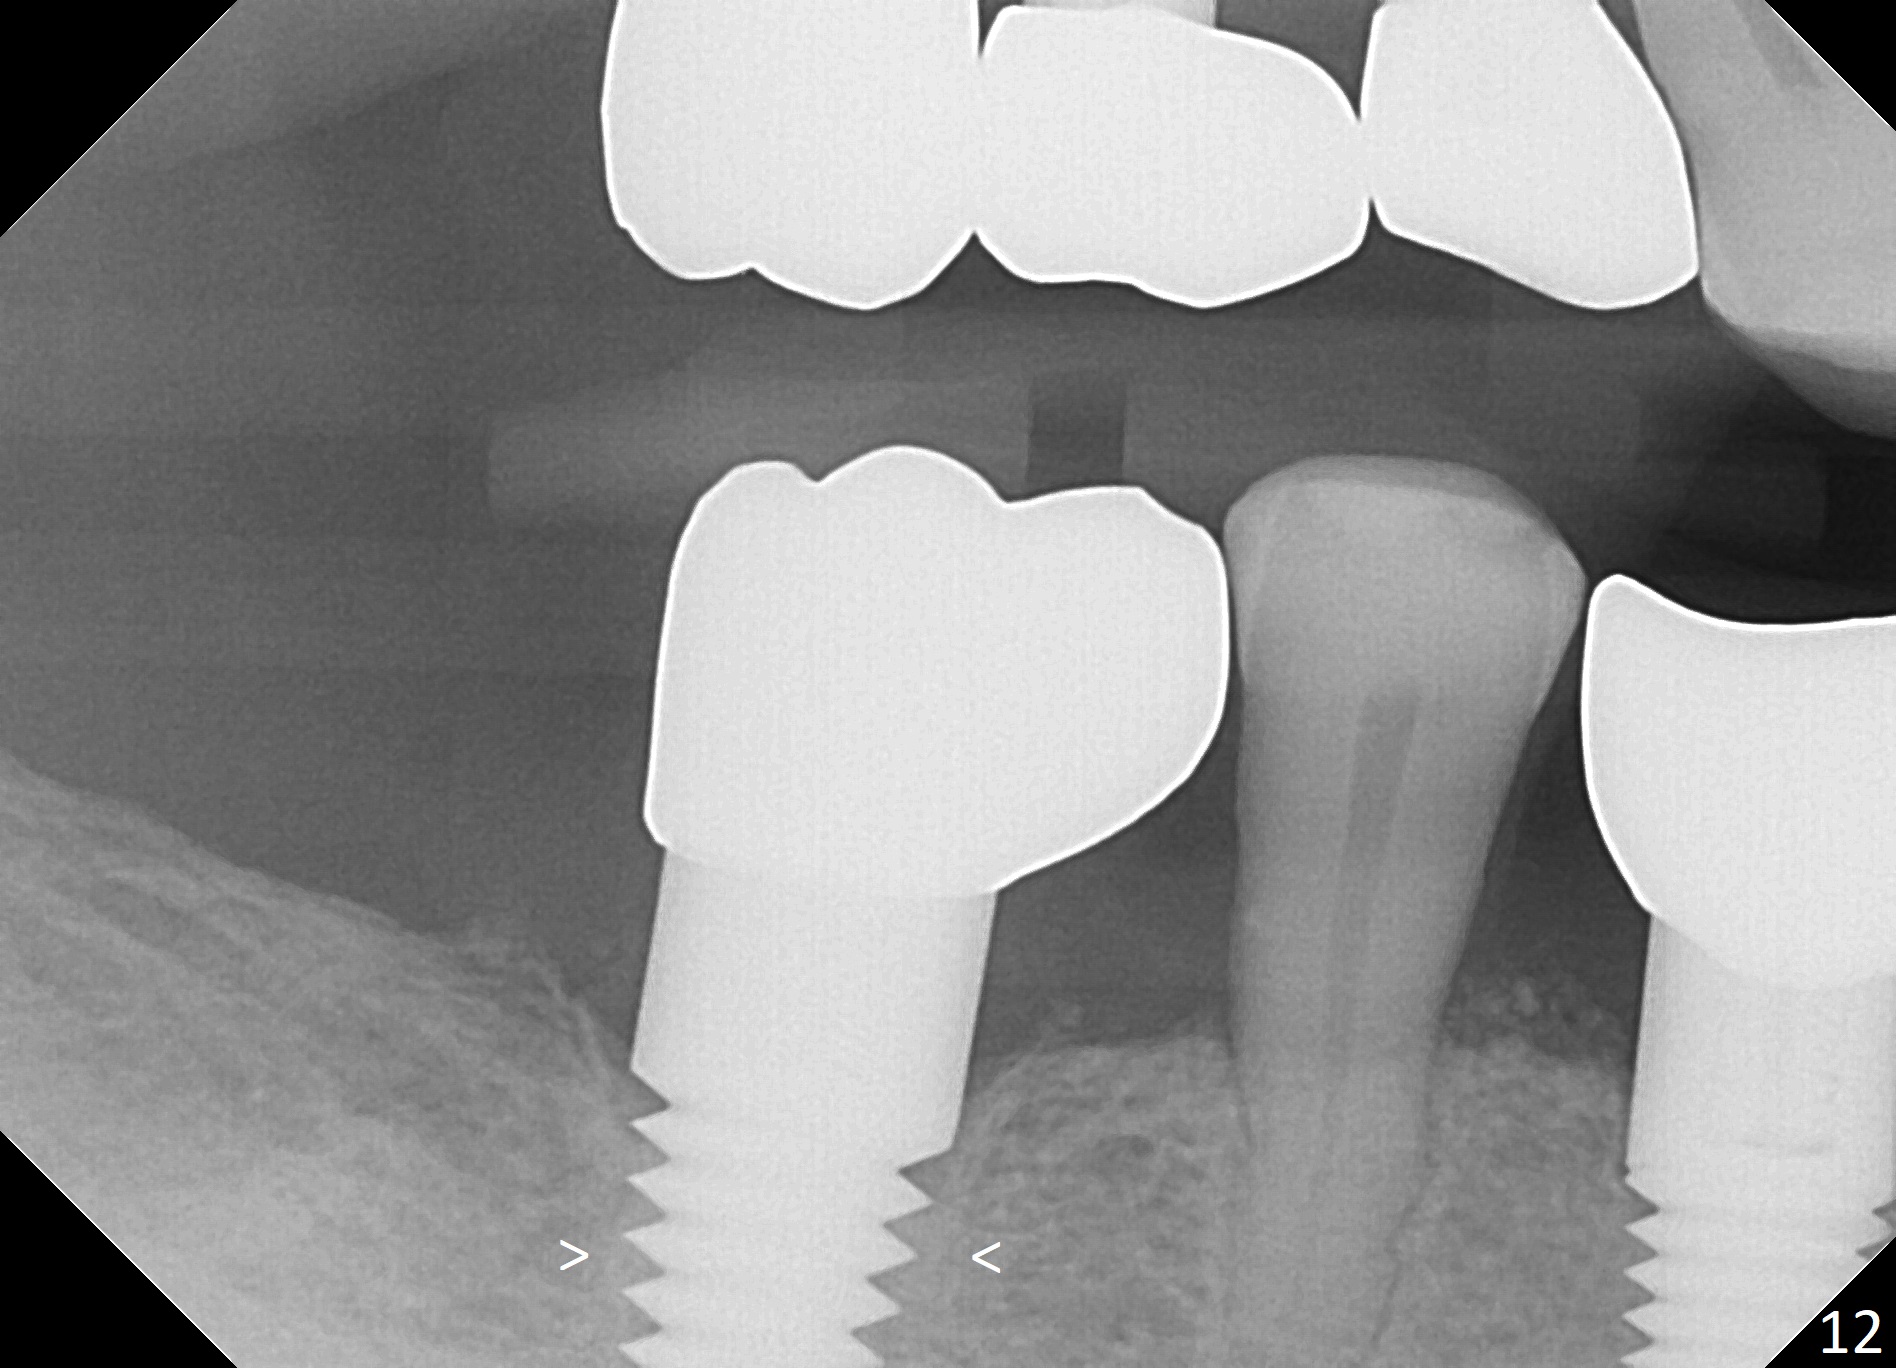

Placement of implant at the site of #30 is a part of full mouth reconstruction aided by orthodontic treatment (1). As Fig.3 demonstrates, the tooth #29 is supraerupted (arrow). Once the implant at the site of #30 is osteointegrated, it is used as one of anchorages (the other is #28 implant crown) to intrude #29. In fact, the patient is uncooperative in orthodontic treatment. There is cortical bone-like formation 3 years postop, 1 year 10 months post cementation (Fig.12 <). There is no bone loss 2 year 11 months post cementation (Fig.13 CT).